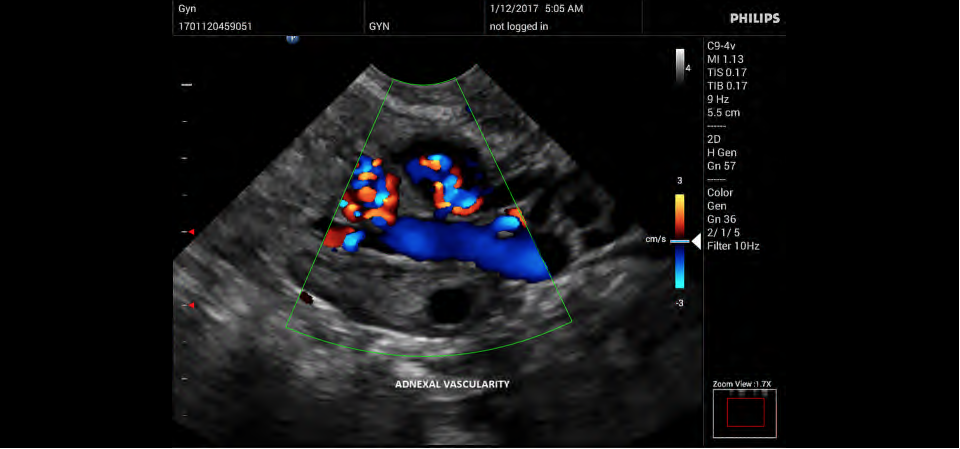

• Акушерство и гинекология;

• Цветное допплеровское картирование

• Конвексный УЗИ датчик Philips C9-4v